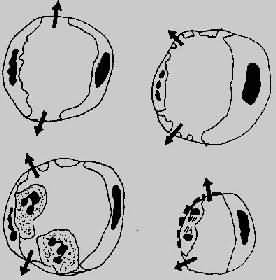

微循环血管通透性的维护,主要依赖于内皮细胞的完整性。在炎症过程中,下列机制可引起血管通透性的增加(图5-2)。

图5-2 血管通透性增加的四种机制模式图

左上图示内皮细胞收缩,累及细静脉;

右上图示直接损伤内皮细胞,累及全部微循环;

左下图示白细胞介导之内皮损伤,主要累及细静脉和毛细血管;

右下图示再生内皮细胞,主要累及毛细血管